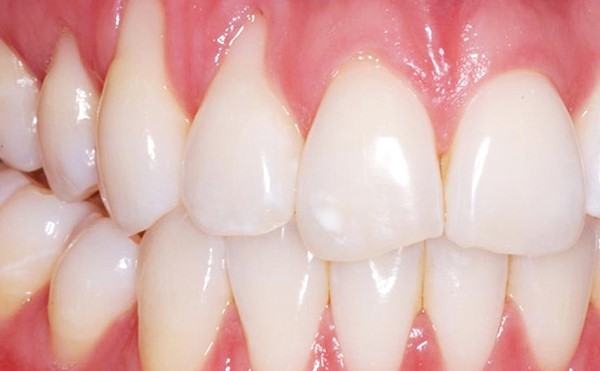

Рецессия десны до и после пластики

Для чего все эти анатомические подробности? Чтобы понимать основную проблему, которая решается с помощью гингивопластики, — а именно рецессию десны. Это такое заболевание, при котором дёсенная ткань на верхней челюсти начинает подниматься, а на нижней — опускаться. В результате обнажается шейка и корень зуба, на которых нет эмали. Рецессия затрагивает отдельные зубы или весь зубной ряд, может быть лёгкой (до 3 мм), средней (3–5 мм) и тяжёлой (более 6 мм). Зрелище в любом случае не очень, особенно на фоне здоровой десны.

Зубы со здоровой и рецессивной десной

До пластики